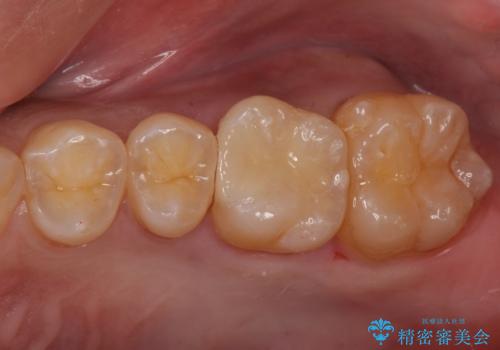

- 奥歯が虫歯になっていたため、セラミックインレーで修復しています。

- 7万円(左上7 emaxプレスインレー 7万円)費用は治療当時の料金となります